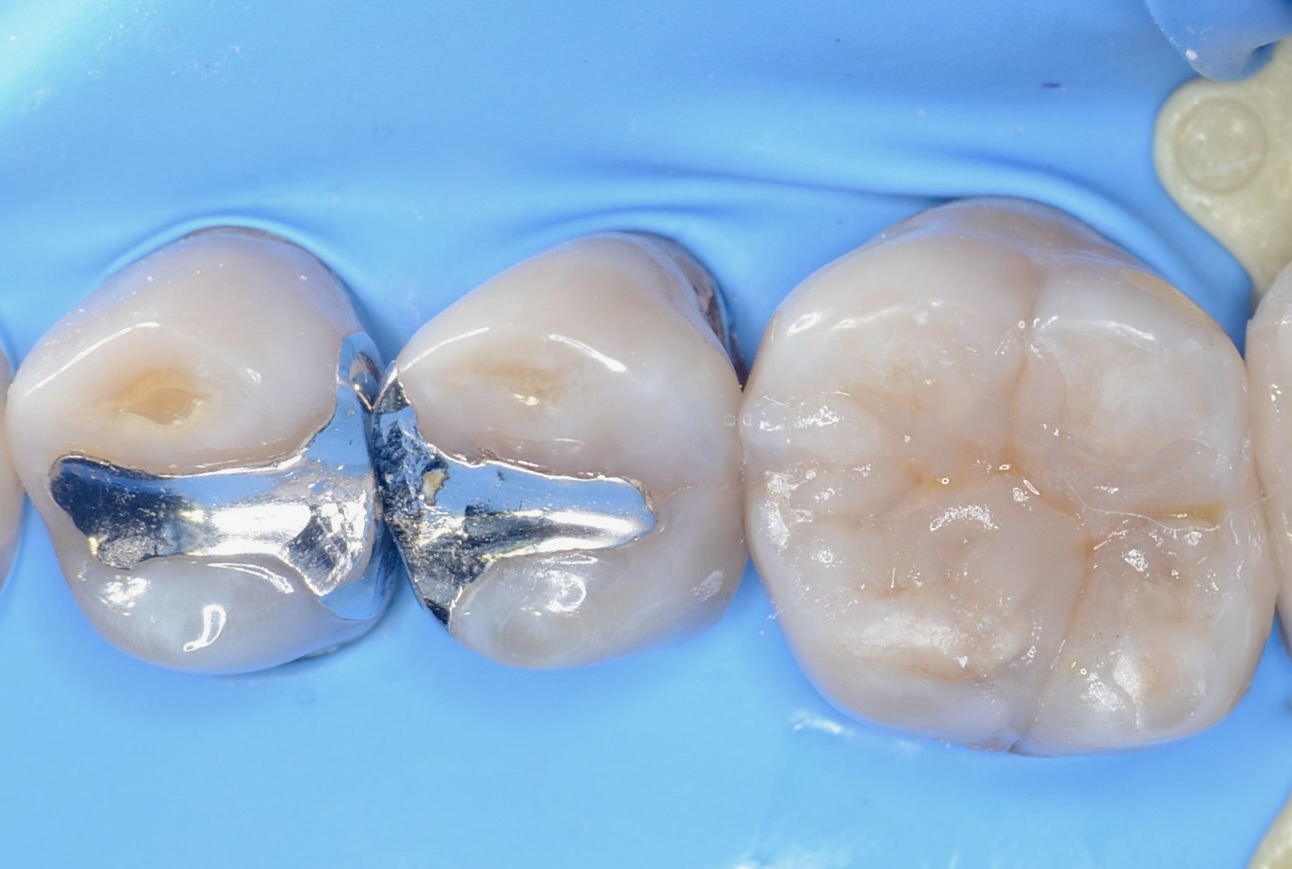

6番のインレーを除去

エナメル質のみを選択的に酸処理をして、接着力を増強させます。 -